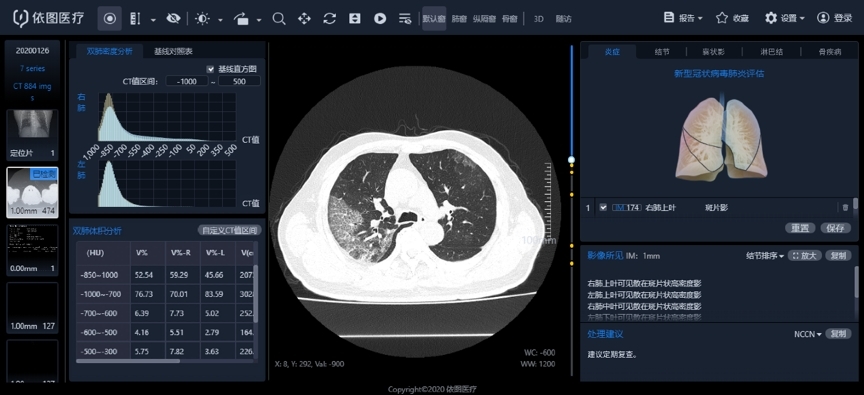

Nell’articolo il Centro ha illustrato i risultati più recenti sull’uso dell’intelligenza artificiale come aiuto per i medici, nelle valutazioni e analisi quantitative intelligenti degli effetti terapeutici sulle nuove lesioni da coronavirus in base alle immagini generate dalla TAC.

Si tratta di uno dei primi sistemi a sfruttare l’IA per la valutazione del COVID-19, un sistema di diagnostica “intelligente” e valutazione qualitativa delle immagini tomografiche che sfrutta algoritmi per l’analisi delle immagini tenendo conto di polmoniti, lesioni locali, lesioni diffuse e del coinvolgimento polmonare.

A detta di chi ha ideato il sistema, questo è in grado di quantificare accuratamente il carico cumulativo della polmonite tramite analisi quantitativa e omiche di elementi chiave nell’immagine che tengono conto di morfologia, range e densità delle lesioni, ottenendo un contrasto dinamico 4D delle intere lesioni polmonari nella TAC, aiutando nel giudizio clinico della condizione, valutare l’efficacia e contribuendo alle prognosi.

Il sistema IA consente di accelerare le procedure di rilevamento, ottenendo risultati in 2-3 secondi. La speranza è che la nascita di tale sistema sia di aiuto nelle strutture mediche-chiave nelle aree colpite dall’epidemia, migliorando l’efficienza dell’analisi quantitativa, contribuendo al trattamento del COVID-19 e alla lotta contro l’epidemia.